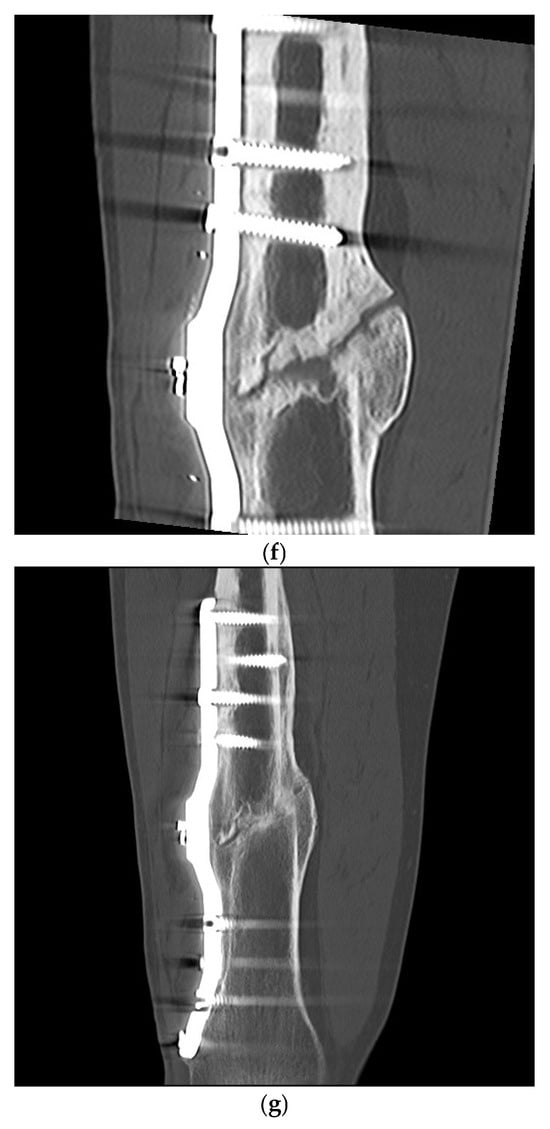

Plate and K-Wire Show Advantages to Nailing for Distal Diametaphyseal Radius Fracture in Children: A Retrospective, Two-Center Study

by Frederik Weil, Lucas Fabarius, Luisa Weil, Paul A. Grützner, Michael Boettcher, Christel Weiß and Stefan Studier-Fischer

J. Clin. Med. 2025, 14(13), 4626; https://doi.org/10.3390/jcm14134626 - 30 Jun 2025

Background/Objectives: Distal forearm fractures are the most common fractures in children. Three surgical techniques are most commonly used at the level of the radial diametaphysis on the distal forearm in children: K-wire, ascending ESIN (elastic stable intramedullary nail) or plate osteosynthesis. The [...] Read more.

Background/Objectives: Distal forearm fractures are the most common fractures in children. Three surgical techniques are most commonly used at the level of the radial diametaphysis on the distal forearm in children: K-wire, ascending ESIN (elastic stable intramedullary nail) or plate osteosynthesis. The aim of this study was to compare these procedures in children with distal diametaphyseal radius fractures regarding operative and functional outcome. Methods: A retrospective study was conducted in two level 1 trauma centers. Children and adolescents aged 2 to 15 years were included. The study period was from January 2010 to December 2022. The hospital information system was used to record patient age, gender, height, weight, fracture location, degree of angular deformity postoperatively, surgical procedure and postoperative complications, which were described in the medical records of the hospital information system. Complications graded by modified Clavien–Dindo–Sink served as the primary outcome. Reduction accuracy, operative and fluoroscopy times, immobilization length and postoperative motion were the secondary endpoints. Results: A total of 213 children were included in the study. K-wire osteosynthesis was performed in 25%, nailing in 19% and volar plate osteosynthesis in 55%. All ESIN were inserted in ascending technique. Complications occurred in 22% of patients and did not differ overall between techniques (p = 0.20). Severe complications were significantly more frequent after ESIN (20%) than after K-wires (7%) or plates (4%) (p = 0.04). Plate fixation achieved the most accurate alignment (≤5° angular deformity in 93% vs. 57% K-wires and 61% ESIN; p < 0.0001) and the fewest late motion restrictions (p = 0.02). K-wire surgery was fastest technique and required the least fluoroscopy, but necessitated the longest postoperative cast. Conclusions: Volar plating combines reliable anatomical reduction with a low rate of major complications and early mobilization, supporting its use in older children whose remodeling potential is limited. K-wires are a swift, minimally invasive option for younger patients, albeit with less precise reduction and prolonged immobilization. Conventional ESIN showed the highest burden of severe complications. Full article